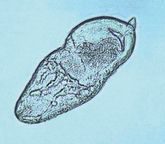

線虫類